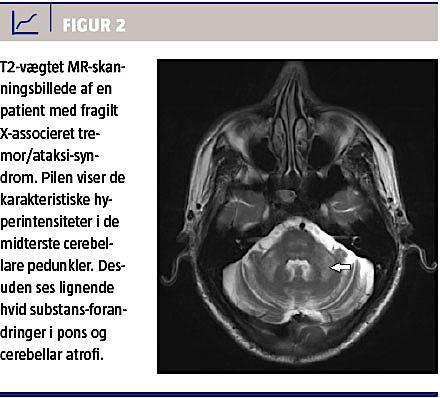

Neuroradiologiske forandringer ved fragilt X-associeret

tremor/ataksi-syndrom

MR-skanning er en vigtig del af FXTAS-diagnosticeringen, idet der typisk ses cerebral og cerebellar atrofi og som et relativt specifikt fund desuden hvid substans-forandringer [16] i de midterste cerebellare pedunkler (MCP) hos ca. 60% og 13% af hhv. mænd og kvinder [13, 16]. Figur 2 er et MR-billede med MCP-tegn. I et nyligt publiceret studie fandt man, at øget intensitet i corpus callosum splenium (CCS) forekom lige så hyppigt som MCP ved FXTAS, og forfatterne foreslog, at CCS skulle indgå som et nyt radiologisk kriterium (Tabel 1) [15].